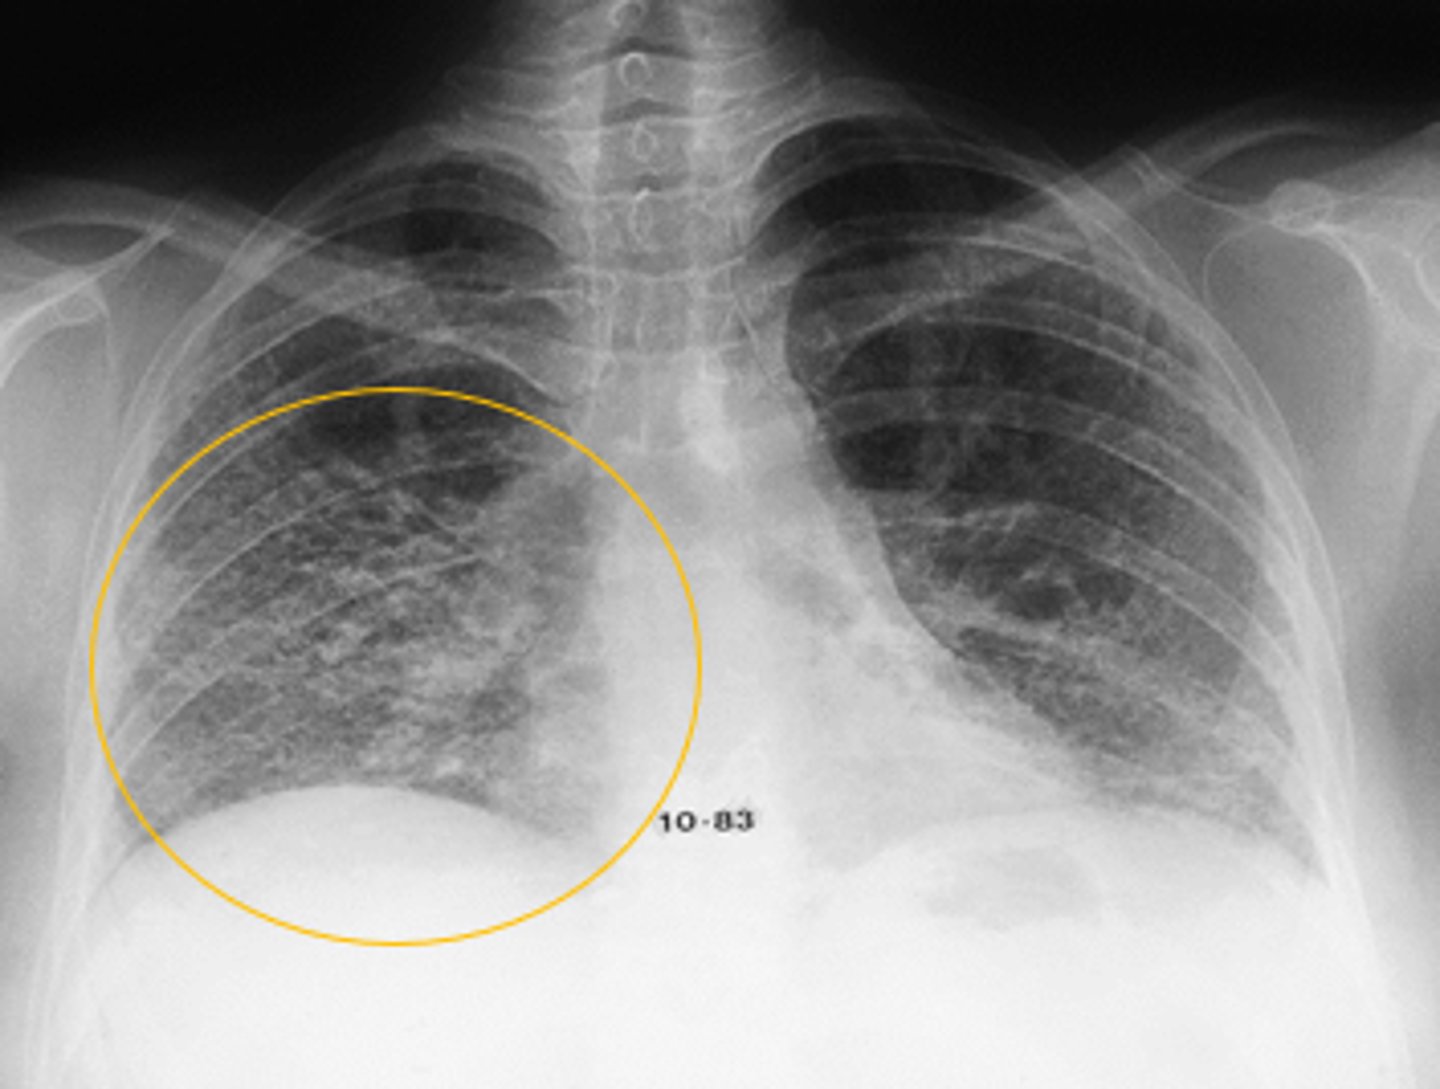

CHF (Kerley B lines- short, horizontal white lines that indicate fluid accumulation)

Interpretation?